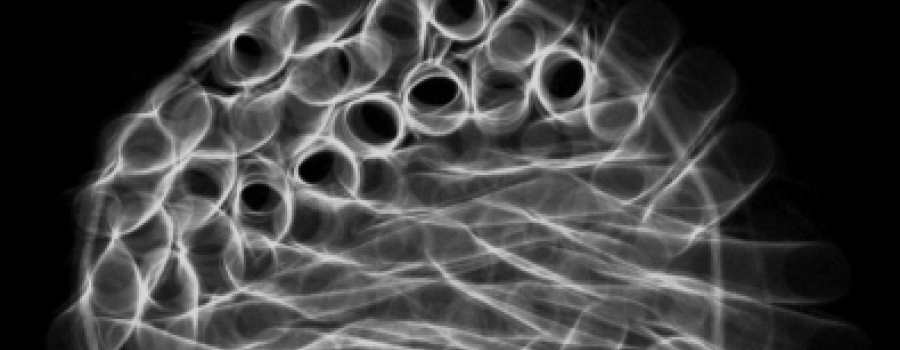

Die Röntgenröhre im medizinischen Einsatzbereich - Ein Vortrag von Dr. Heinrich Behner Siemens AG (Teil 3)